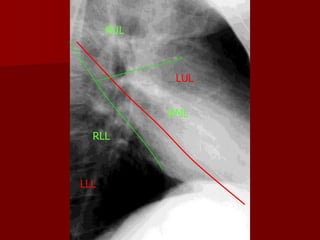

RUL

LUL

RML

RLL

LLL

Oblique fissure more clearly seen on Lateral view from

T4-T5 vertebrae to reach the diaphragm and 5 cm

behind the costophrenic angle on left And just behind

the angle on right.

Horizontal fissure more clearly Seen on P.A view

extending from Right hilum to 6th rib in the axillary line